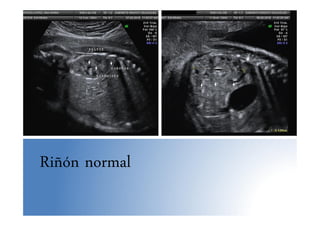

• Examen ecográfico:

– Vejiga: arterias umbilicales a ambos lados, en 3º T

se llena y vacía +/- cada 30 min.

– Riñones:

• Medida de pelvis renales en un corte transversal, a

partir de la semana 33 el punto de corte para el Dx de

ectasia piélica se sitúa en 7 mm. en sentido AP in to in

• En 3º trimestre: borde ecogénico (grasa perirrenal),

diferenciación corteza, pirámides y pelvis

• Medida del riñón: EG + 10 mm

Riñón normal